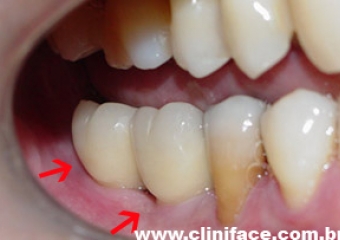

Imagens com prótese fixa em porcelana sobre implantes do caso finalizado em janeiro de 2009